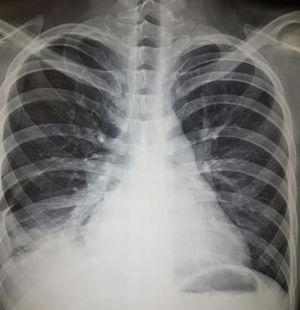

Diagnóstico. Entre los diferenciales se incluyen dolor musculoesquelético, embolismo pulmonar, infección, falla cardiaca, uremia y neoplasia. El análisis del líquido pleural es la principal herramienta diagnóstica. Típicamente, se trata de un exudado con elevación discreta de leucocitos, predominio de mononucleares (también hay polimorfonucleares) y niveles de glucosa normales o ligeramente bajos. El diferencial principal es con artritis reumatoide (AR), caracterizado por mayor elevación de leucocitos y DHL así como glucosa baja2. El papel que tiene la detección de anticuerpos antinucleares (ANA) en líquido pleural para el diagnóstico de pleuritis lúpica es controversial. Dos estudios recientes17,18 han reportado ANA a títulos >1:160 con sensibilidad del 85 al 90% y especificidad del 80% para diagnóstico de pleuritis lúpica en pacientes con lupus, sin embargo, títulos elevados también pueden encontrarse en otras entidades. En la figura 1 se muestra evidencia de derrame pleural en paciente con lupus que refirió datos clínicos de afección pleural.

Mujer de 22 años con LEG de 3 años de evolución caracterizado por manifestaciones cutáneas y musculoesqueléticas. Acude por cuadro de un mes de evolución caracterizado por dolor de tipo pleurítico y disnea. La radiografía de tórax simple reveló imágenes radiopacas que obliteran ángulos costodiafragmáticos compatibles con derrame pleural el cual fue abordado y posteriormente atribuido a actividad de su enfermedad de base.